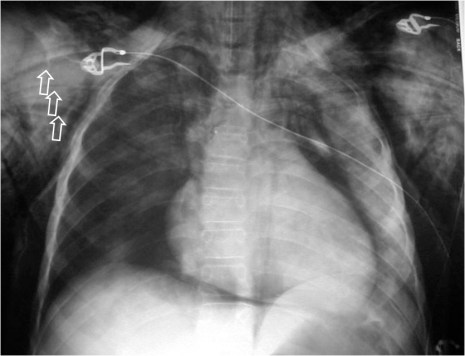

Signo de enfisema subcutáneo en la radiografía de tórax, que se ve como unas líneas radiolucentes que siguen la distribución de las fibras de los músculos pectorales mayores. En la imagen podemos verlo de forma bilateral (en la derecha se señalan con flechas). En esta misma radiografía pueden verse, además, signos de neumomediastino como el signo de la V de Naclerio y el signo de la V de las venas braquiocefálicas (ver el aparatado de Mediastino).

El nombre del signo viene dado por su parecido con las estriaciones que tienen las hojas de este curioso árbol. El Ginkbo biloba es el árbol más antiguo que existe, de forma que no tiene parientes cercanos en la clasificación taxonómica. Era conocida su existencia por restos fósiles y se pensaba que estaba extinguido. Un científico alemán en el siglo XVII lo encontró en Japón y lo trajo a Europa. En Japón es común encontrarlo en la proximidad de monasterios y era conocido por sus propiedades medicinales. Una curiosidad más es que un ejemplar de esta árbol situado a cerca de un kilómetro de donde cayó la bomba de Hiroshima, comenzó a rebrotar apenas un año después, por lo que allí es todo un símbolo de supervivencia y regeneración. Con esta breve historia no se nos olvida el valor de este signo.